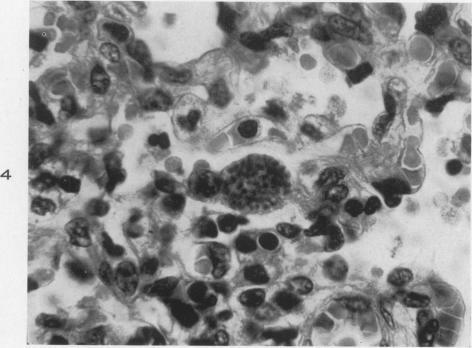

Systemic Infantile Toxoplasmosis.

Am J Pathol. 1946 Jul;22(4):779-95.